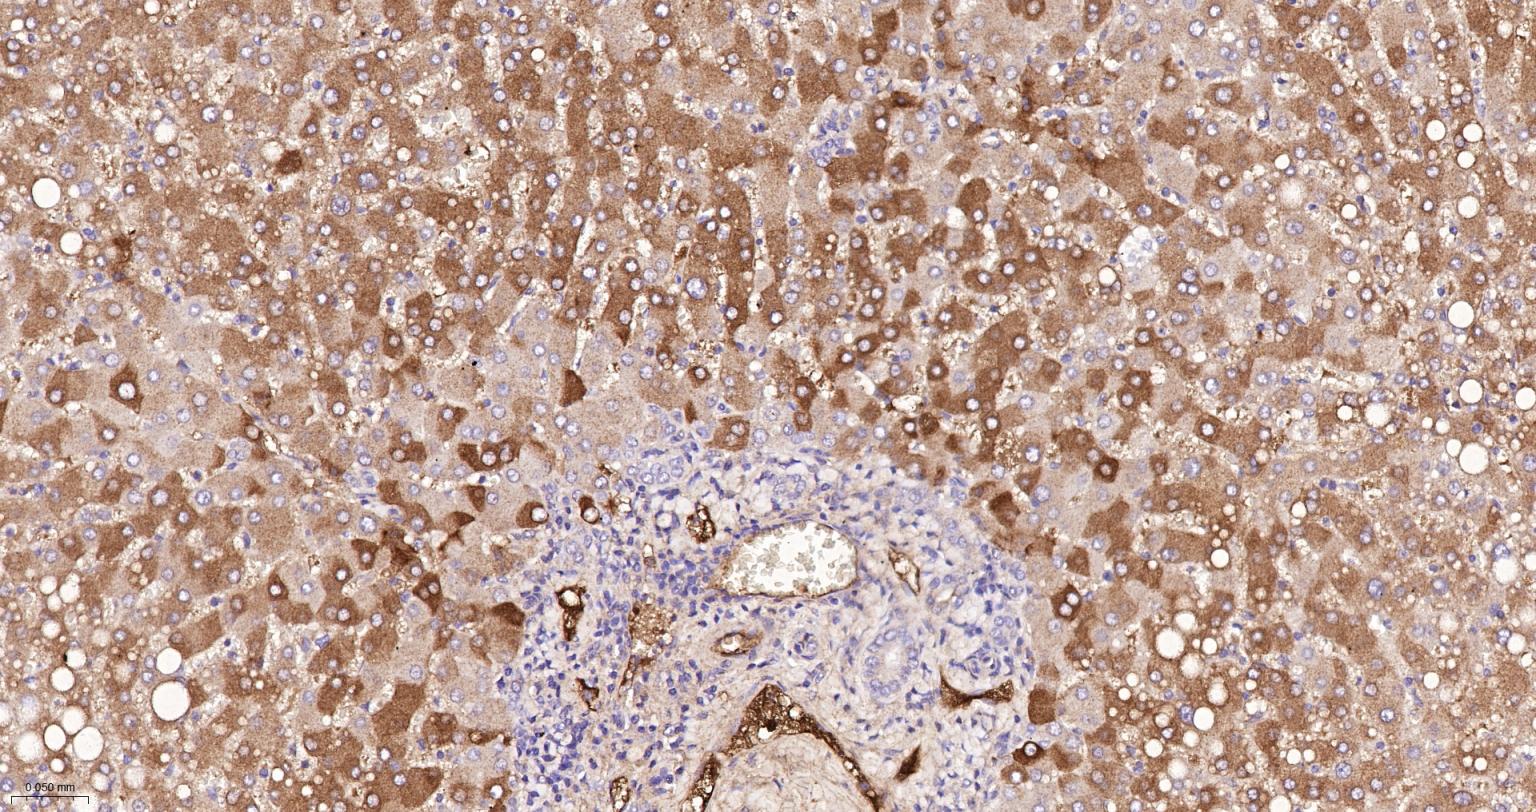

Paraformaldehyde-fixed, paraffin embedded Human Liver Cancer; Antigen retrieval by boiling in sodium citrate buffer (pH6.0) for 15 min; The section was incubated with Factor X Monoclonal Antibody, Unconjugated (bsm-61666R) at 1:200 overnight at 4°C, followed by conjugation to the bs-0295G-HRP and DAB (C-0010) staining.